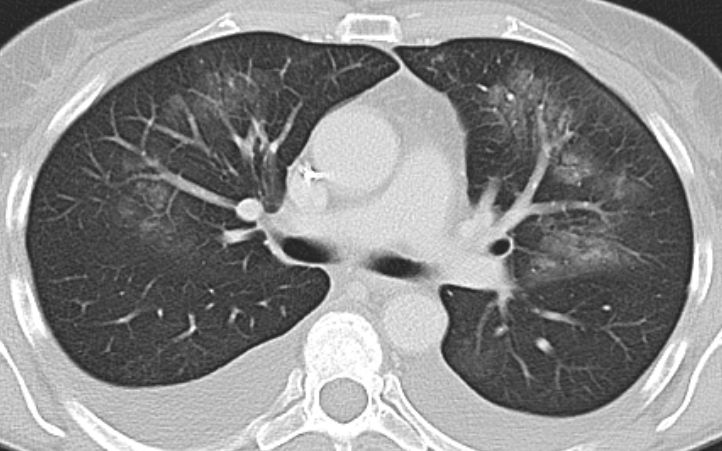

| Lunge | 57-jährige Frau mit Magenkarzinom, die nach FLOT eine Alveolitis mit respratorischer Insuffizienz entwickelte.![]() | |||||||||||||||||||||||